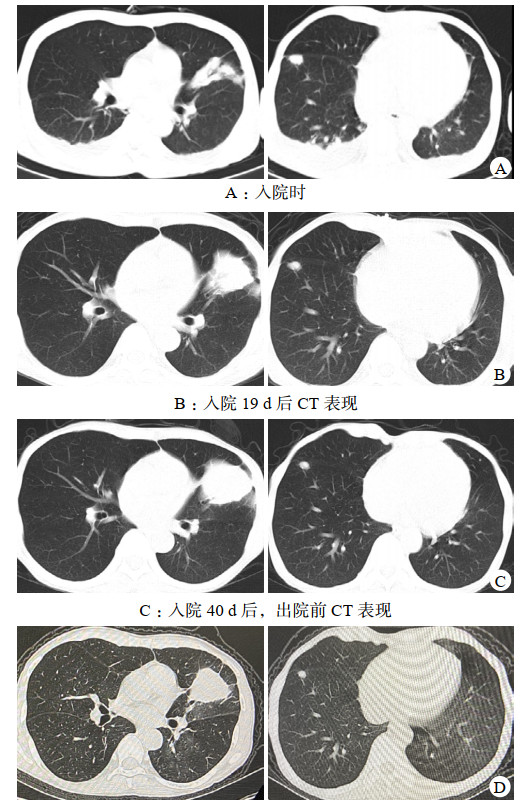

尿常规:蛋白4+,红细胞+,白细胞+;血常规:白细胞4.21×109/L,淋巴细胞百分比2.4%,中性粒细胞百分比90.7%,血红蛋白67 g/L,血小板69×109/L,CRP 30.3 mg/L;血生化:PCT 2.3μg/L,白介素-6 36.59 ng/L,白蛋白27.3 g/L,球蛋白21.4 g/L,尿素48.1 mmol/L,肌酐806.9 μmol/L,总二氧化碳17.5 mmol/L;免疫球蛋白G 8.38 g/L;CD3+T 141个/uL,CD4+T 69个/uL,CD8+T 64个/uL,CD20+B 9个/uL;CT:两肺可见大片状及结节样实性密度影,左肺上叶下舌段病灶内可见支气管充气征(图 2A);

图 2 患者入院与出院后CT影像

患者入院当日停吗替麦考酚酯、他克莫司,强的松减量至10 mg每日1次口服,隔日血液透析,送检血液mNGS,次日报告:马尔尼菲蓝状菌(序列数4 794)、人类疱疹病毒5型(序列数42)(入院10日后血培养、中段尿培养报马尔尼菲蓝状菌,痰培养、痰浓缩集菌抗酸菌检测阴性)。查血液真菌G试验28.82 pg/mL,GM试验2.59,血液INF-γ释放试验阴性。予莫西沙星0.4 g每日1次静滴、伏立康唑0.2 g每日2次静滴、两性霉素B脂质体(峰克松)逐步加量至50 mg每日1次静滴联合抗感染,监测伏立康唑血药谷浓度3.53 μg/mL,17 d后停两性霉素B脂质体。期间双眼结膜红肿充血加重,伴不自主流泪,右鼻翼、鼻腔、左侧嘴角处溃疡扩大,先后加用妥布霉素滴眼液、卡波姆滴眼液、金霉素眼膏、莫匹罗星软膏外涂。入院19 d后仍有间断发热,CRP升至44.6 mg/L,PCT升至4.32 μg/L,复查CT左肺上叶见类圆形及斑片状密度增高影较前增大,右肺下叶叶间裂处可见多发斑片状密度增高影(图 2B)。行支气管镜检查,术中左舌叶上侧支一亚支可见球型新生物堵塞管腔,表面粗糙,触之易出血(图 3),病理活检示组织急慢性炎症,局部见大量泡沫样组织细胞反应,抗酸染色未发现阳性菌(图 4)。肺泡灌洗液(BALF)GM试验0.84,BALF mNGS报烟曲霉(序列数11),马尔尼菲蓝状菌(序列数5),哥伦比亚分枝杆菌(序列数4989),人类疱疹病毒5型(序列数162),人类疱疹病毒4型(序列数6)。痰液及BALF分枝杆菌培养均阴性。明确诊断为“⑴播散性马尔尼菲蓝状菌病;⑵肺非结核分枝杆菌病(哥伦比亚分枝杆菌);⑶侵袭性肺曲霉菌病(烟曲霉)”。考虑利福平显著影响伏立康唑血药浓度,未加用利福平。抗感染方案调整为伏立康唑0.2 g每日2次静滴、乙胺丁醇0.75 g每日1次口服、阿奇霉素0.5 g每日1次口服、利奈唑胺0.6 g每日2次静滴。患者静滴利奈唑胺期间出现胸闷、恶心,停利奈唑胺,恢复莫西沙星0.4 g每日1次静滴,监测体温峰值逐步下降,出院1周前未再发热。在院43 d,出院前CRP 1.1 mg/L,PCT 0.342 μg/L,血液真菌G试验9.9 pg/mL,GM试验0.22,CD4+T 143个/uL,双侧眼睑红肿好转,右侧鼻翼、鼻腔及左侧嘴角溃疡消退(图 1b)。复查CT左肺上叶、右肺下叶叶间裂处仍见高密度影(图 2C)。患者出院后继续口服伏立康唑、阿奇霉素、乙胺丁醇、莫西沙星抗感染,期间未再发热,常规血液透析治疗,3个月后复查CD4+T 314个/uL,CT左肺上叶团块影和右肺下叶叶间裂结节体积较前明显缩小(图 2D)。